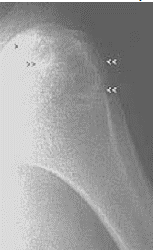

Buttress

periosteal reaction caused by slow-growing tumors that provoke cortical thickening